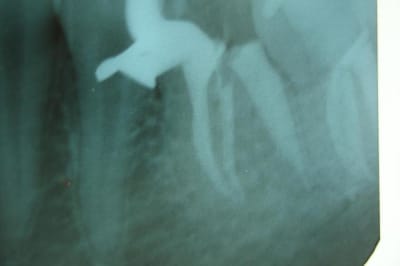

(mes photos : radio ortho et excentrée, "vue de dessus", tenons de chez Anthogyr, mordançage et tenon, et malheur de malheur pas de photo du résultat car plus de batterie dans ce satané appareil.=

Tes radios sont floues et la teinte étrange.

Canaux mésiaux semble avoir été un poil trop ouverts.

La racine mésiale semble mince

Bravo à Cingulum, il s'agit bien d'argentique photographié.

Désolé pour la qualité des radios, je sais que l'iconographie est importante.